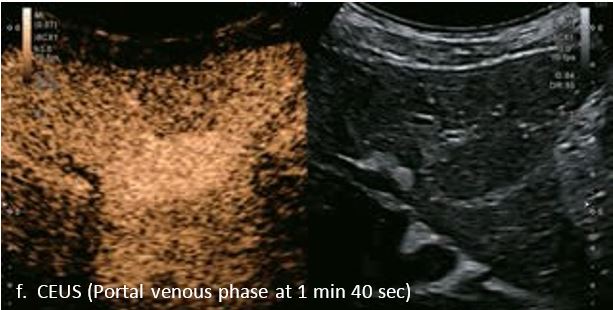

LI-RADS 4 множинні ГЦК

Це випадок 60-річної жінки з декомпенсованим цирозом печінки з асцитом. На сірошкальному зображенні можна виявити два вогнищевих ураження, розміром 21 мм і 10 мм відповідно, розташовані в сегменті 5. Оскільки дослідження методом зсувної хвилі на апараті Canon виконується штовхаючим імпульсом, пацієнтам з асцитом не можна проводити дослідження за допомогою зсувної хвилі, для визначення стадії фіброзу. На ранній артеріальній стадії гомогенне гіперехогенне підсилення спостерігається в обох ураженнях. Ураження є ізоехогенними в портальній венозній та пізній фазах, вимивання не спостерігається через 6 хвилин після ін'єкції, тому ці ураження були класифіковані як LI-RADS 4, ймовірна ГЦК. Важливо знати, що LI-RADS 5 - це ГЦК зі 100% вірогідністю, і вона не потребує біопсії. Значна кількість LI-RADS M (ймовірно або точно злоякісні, але не специфічні для ГЦК) і LI-RADS 4 (ймовірна ГЦК) насправді являються ГЦК.

Малюнок 11